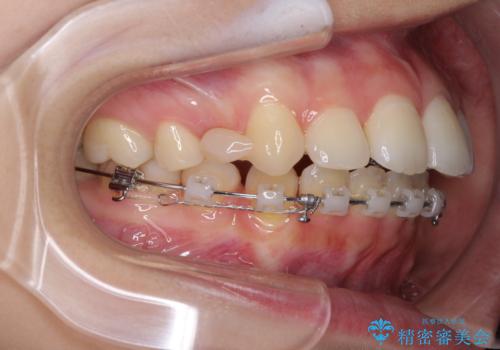

- ハーフリンガル

目立たない装置が希望であったため、上顎が裏側装置である、ハーフリンガル装置を選択されました。

3年半ほどで終わる予定でしたが、途中引っ越し、出産、引っ越し、出産を繰り返し、なかなか来院することができず、装置を外すまでに8年以上の期間がかかってしまいました。